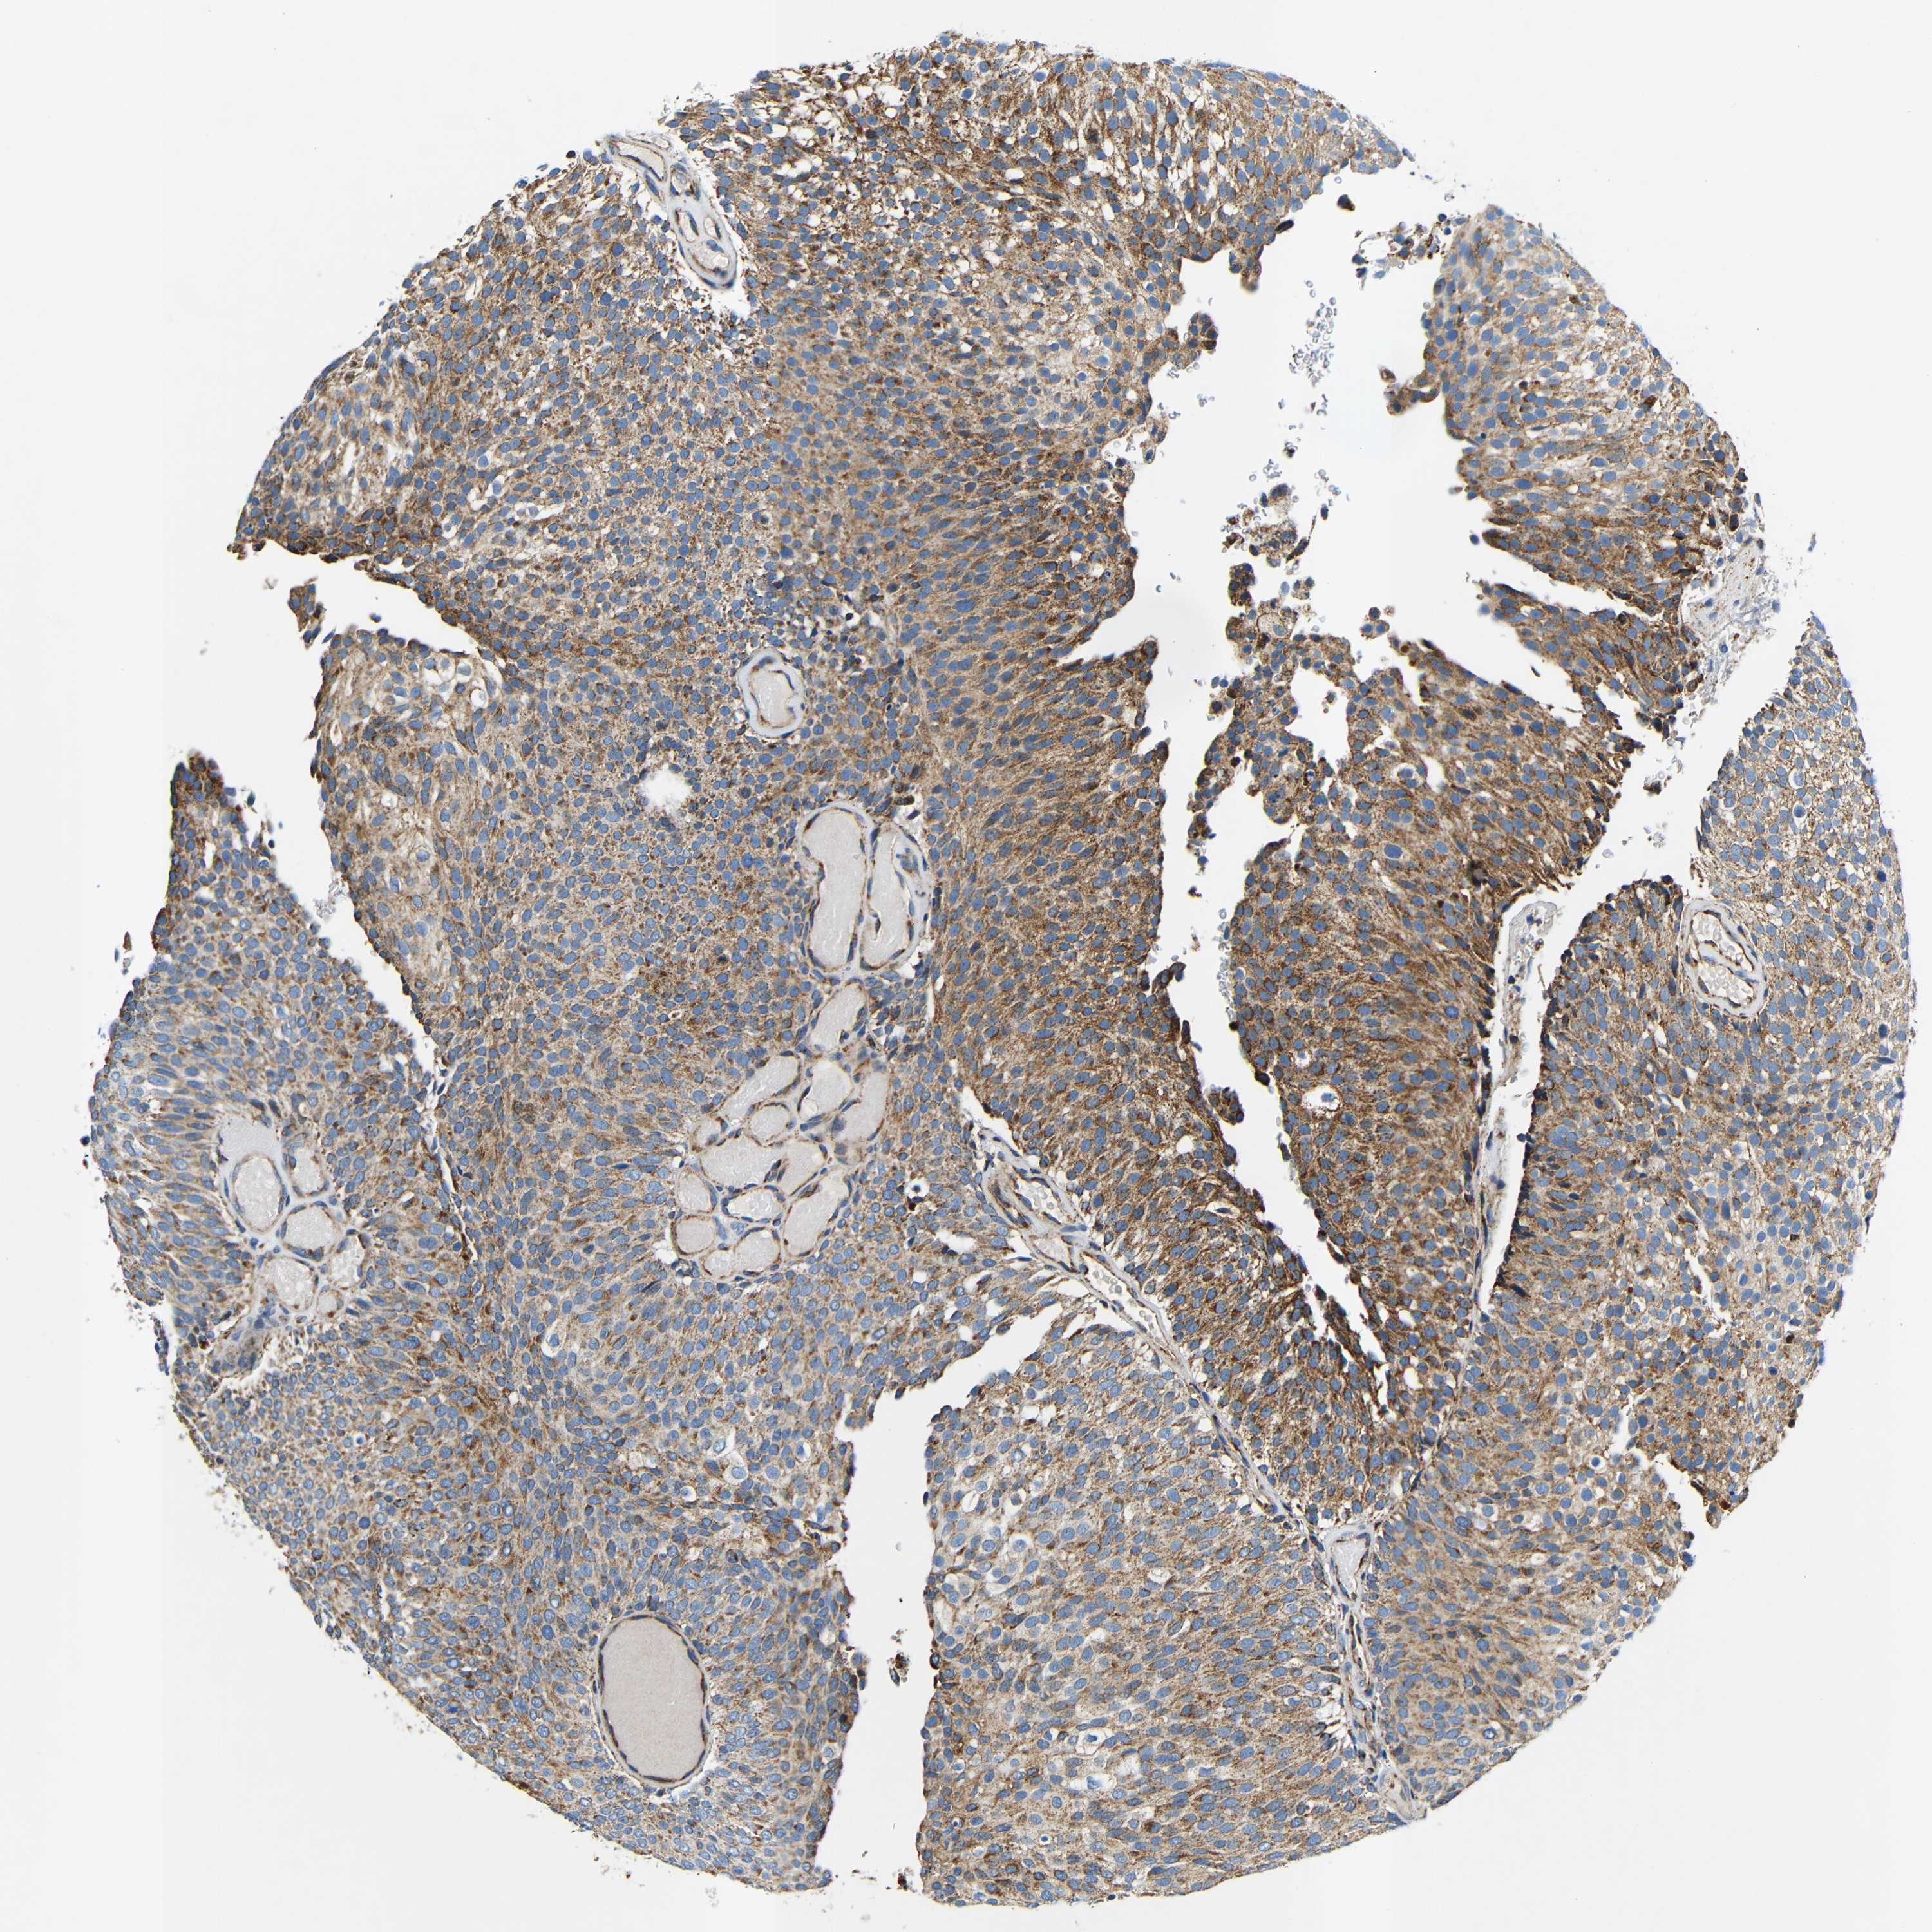

UROTHELIAL CANCER - Protein expressioni

A mouse-over function shows sample information and annotation data. Click on an image to view it in a full screen mode. Samples can be filtered based on level of antibody staining by selecting one or several of the following categories: high, medium, low and not detected. The assay and annotation is described here.

Note that samples used for immunohistochemistry by the Human Protein Atlas do not correspond to samples in the TCGA dataset.

Antibody stainingi

Antibody staining in the annotated cell types in the current human tissue is reported as not detected, low, medium, or high, based on conventional immunohistochemistry profiling in selected tissues. This score is based on the combination of the staining intensity and fraction of stained cells.

Each image is clickable and will lead to virtual microscopy that enables deeper exploration of all samples and also displays staining intensity scores, fraction scores and subcellular localization as well as patient and tissue information for each sample.

Antibody HPA012955

Staining

High

Medium

Low

Not detected

Intensity

Strong

Moderate

Weak

Negative

Quantity

>75%

75%-25%

<25%

None

Location

Nuclear

Cytoplasmic/membranous

Cytoplasmic/membranous,nuclear

Urothelial carcinoma, Low grade

Urothelial carcinoma, High grade